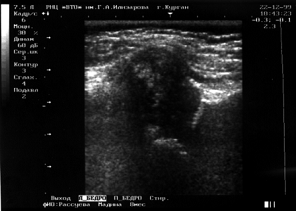

При УСГ сканировании тазобедренных суставов у здоровых детей углы α и β равнялись соответственно 600 и более; 550 и менее. На рисунке 1 представлен центрированный физиологически зрелый сустав ребенка в возрасте 2 месяцев, показана также схема проведения касательных линий относительно костной, хрящевой крыши и контура вертлужной впадины и расчета измеряемых углов α и β (угол α=68º, угол β=47º; хрящевая крыша охватывает головку, костный эркер прямой, костная крыша вертлужной впадины развита достаточно).

Рис.1.Сонограмма  центрированного физиологически зрелого тазобедренного сустава 2- месячного ребенка (сканирование  по методике Графа)